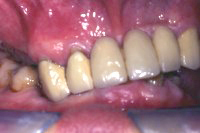

Ein 79 Jahre alter Mann wünschte sich auf den 80igsten Geburtstag, wieder mal richtig in ein Steak beissen zu können. Die Gebissituation war sehr ungünstig (Abb. 1) und so unangenehm, dass er zum Essen eine Aufbissschiene im Oberkiefer tragen musste (Abb. 2, 3), ansonsten er sich mit seinem eigenen oberen Eckzahn bei Kieferschluss in das Unterkieferzahnfleisch gebissen hätte(Abb. 4).

Im Unterkiefer habe ich einige parodontal schwer geschädigte Zähne gezogen und zwei Monate später sieben Implantate gesetzt, wobei bei einigen kleinere Augmentationen gemacht wurden (advanced implantology). Nach sechswöchiger Einheilung der Implantate (Abb. 5 und 6) wurden die Aufbauten in die Implantate eingeschraubt und die verschiedenen Brücken festsitzend zementiert.